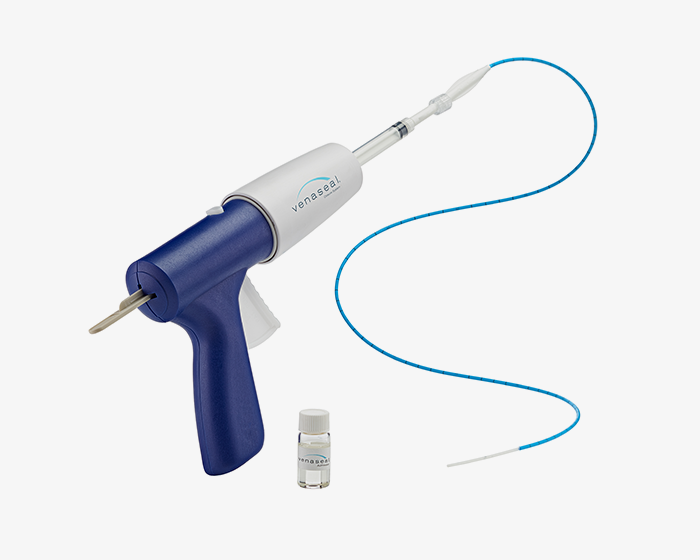

의료용 생체 접착제를 활용하여 피부 표면에서 압박하여 혈관을

접착시키는 방법으로 물리적 손상이 없다는 장점이 있습니다.

베나실은 인체 친화적인 의료용 접합제를

질환이 있는 원인 정맥에 주입하여

정맥을 폐쇄하는 하지정맥류 치료 의료기기입니다.